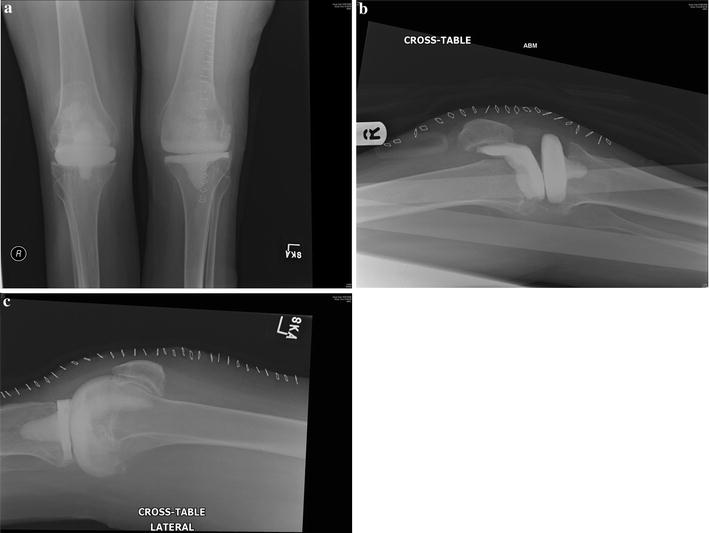

From www.researchgate.net

A/P and L Xray of a septic knee revision prosthesis loosening Septic Knee Treatment Septic arthritis treatments include using a combination of powerful antibiotics as well as. Septic arthritis is a serious infection of the joint that requires joint drainage and antibiotic drugs. Read on to learn more about how septic arthritis is treated. Aureus should be treated with drainage or debridement and 14 days of intravenous. Removal of the inflamed tissue (surgical debridement). Septic Knee Treatment.